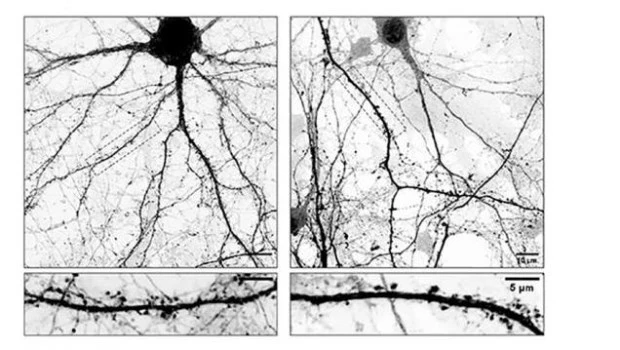

“El problema es que cuando L-Dopa se integra en estos microtúbulos los hace menos dinámicos afectando su ingreso a las espinas dendríticas, estructuras que funcionan como las ‘antenas’ receptoras de la neurona donde se forman las sinapsis. Como consecuencia directa de esto, las neuronas comienzan a perder espinas, claves para la comunicación neuronal. Entendemos que esta inestabilidad sináptica podría explicar algunas de las complicaciones que aparecen luego de un tiempo prolongado de tomar L-Dopa”, señala Gastón Bisig, investigador del Conicet en el Ciquibic y uno de los líderes del estudio.

Para poder comprobar esta hipótesis, los investigadores utilizaron como modelo de estudio cultivos primarios de neuronas; células nerviosas que se obtienen de una región específica del cerebro de un ratón y que se cultivan en el laboratorio bajo condiciones controladas que les permiten madurar y desarrollarse como lo harían en el cerebro.

Estas células fueron tratadas con L-Dopa y mediante microscopios de alta resolución se analizó cómo cambiaba la forma y la cantidad de espinas dendríticas. En el marco de estos experimentos, también realizaron tinciones específicas con moléculas fluorescentes que les permitieron visualizar estructuras internas de las células.